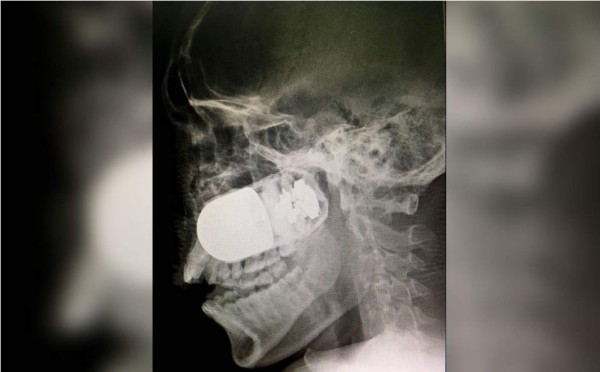

Médicos colombianos extrajeron del rostro de un soldado una granada incrustada durante un accidente con un lanzagranadas, un arriesgado procedimiento que debió realizarse en el aparcamiento del Hospital Militar de Bogotá ante el temor de que el explosivo estallase en quirófano.

La grabación de la delicada intervención, difundida hoy en redes sociales, muestra cómo el equipo quirúrgico retira del pómulo derecho del uniformado un cilindro de unos cinco centímetros de longitud.

La granada se alojó en el rostro del soldado profesional Leandro José Luna el pasado domingo en el departamento de Arauca, fronterizo con Venezuela, cuando los militares patrullaban en una zona cercana al río Tame, detallaron medios locales.

En la capital colombiana fue operado con éxito el domingo en el parqueadero del Hospital Militar, donde se decidieron a operarle por temor a que el explosivo estallara en el quirófano.